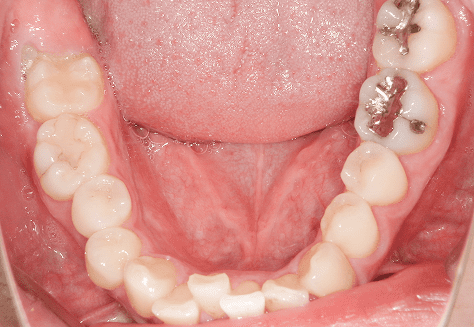

S.K

治療前

治療後

主訴

歯が重なっていて気になる。前歯が出ていて唇が閉じにくい。ハミガキがしにくい。

診断

上顎前突・叢生

年齢/性別

20代/男性

抜歯部位

上下第三大臼歯

使用装置

上下インビザライン

保定装置

上下ビベラリテーナー

料金

初回資料採得・・・・・・・30,000円

診断料・・・・・・・・・・33,000円

動的治療終了時資料採得・・5,500円 -

基本料金

990,000円

診察料金

1,100円×33回

治療期間

3年5カ月